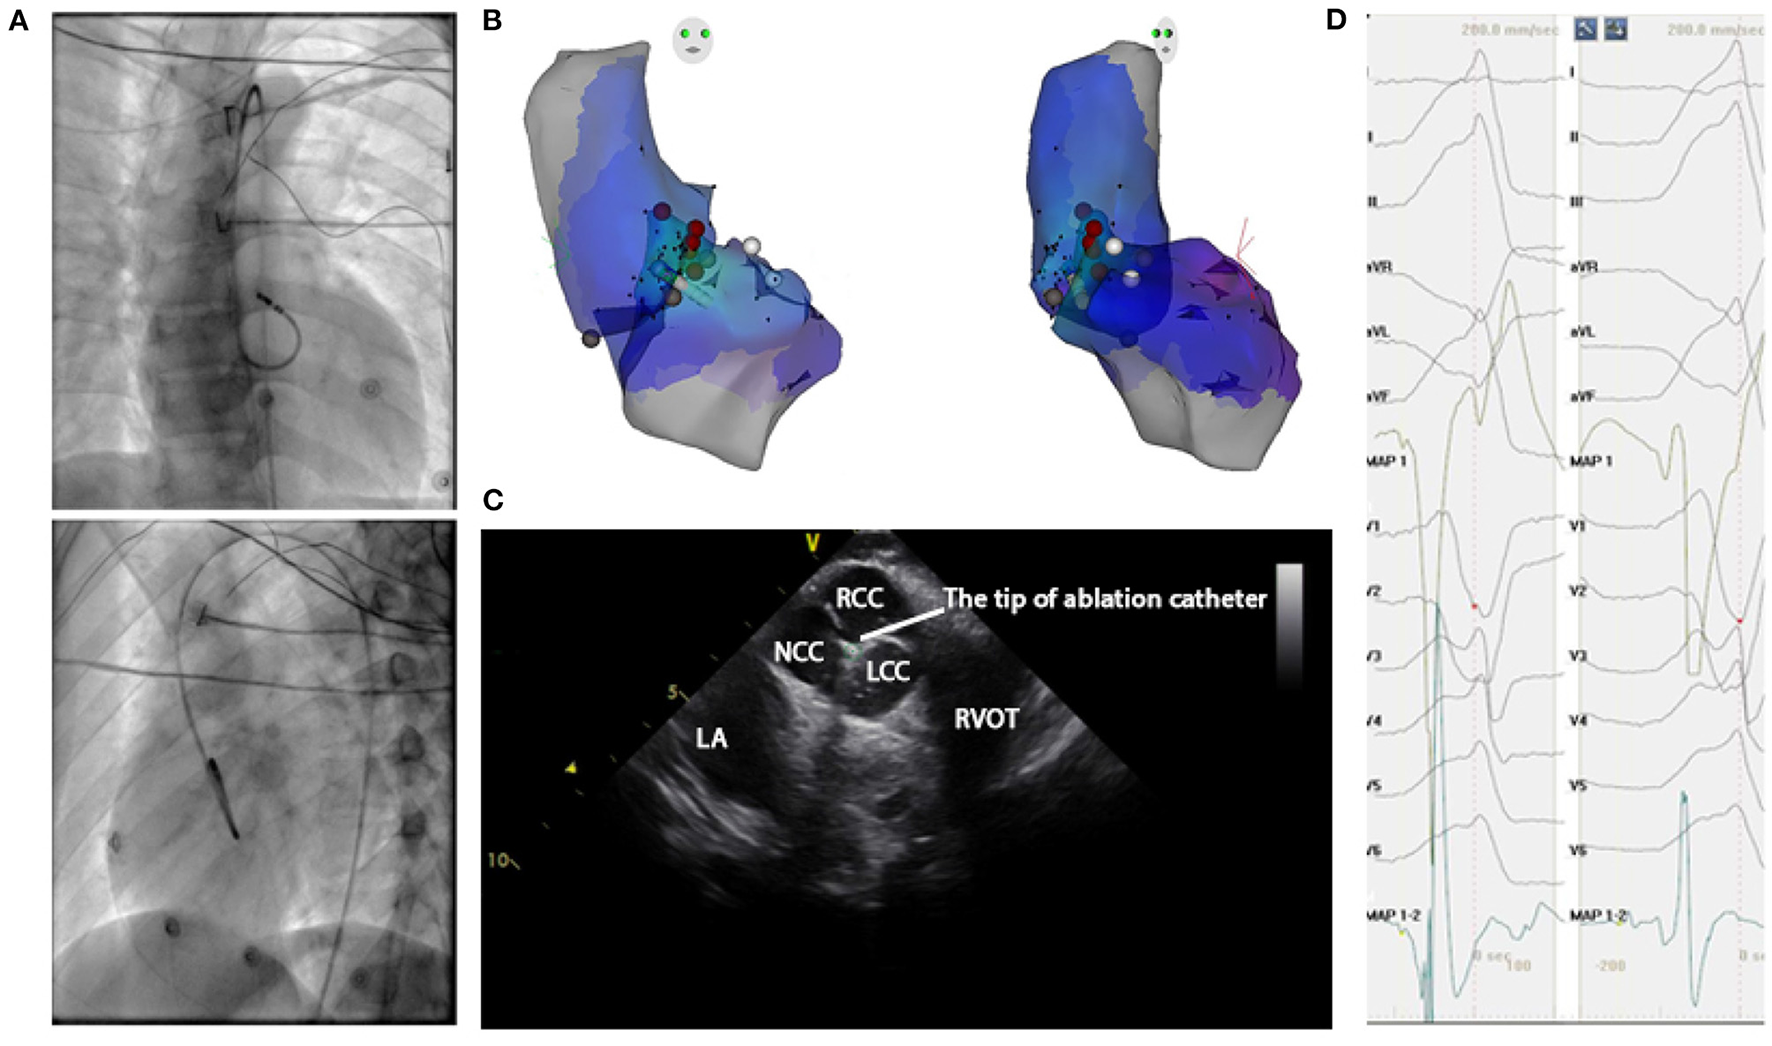

Administration of antiarrhythmic drugs had been stopped for at least five half-lives before the inception of the ablation procedure. A 4.0-mm 7F irrigated-tip ablation catheter (Navistar, Biosense Webster, Diamond Bar, CA) was initially placed in the RVOT for mapping. Both fluoroscopy and electroanatomic mapping systems (CARTO, Biosense Webster, Diamond Bar, CA, USA or NavX Velocity, St. Jude Medical, St. Paul, MN, USA) were used to localize the anatomical position of the catheter ablation for all cases in this study. For a total of 187 patients enrolled after 2018, the echocardiogram was used to identify specific anatomical structures such as cusps and papillary muscles. For instance, Figure 4 presented the fluoroscopy, 3-dimensional mapping, intracardiac echocardiography, and activation mapping for a patient who has VT originating from LCC-RCC commissure of LVOT. Using point by point mapping, anatomical aggregated maps were created. Activation mapping was performed in all patients during VT and PVC. Pace mapping was also performed, with the lowest pacing output (2 to 20 mA) and pulse width (0.5 to 10 ms), to capture the ventricular myocardium at the site of the earliest activation. If suitable ablation sites for the RVOT origin were not located or ablation failed to abolish the arrhythmia, extended mapping to the LVOT site was deployed via a retrograde aortic approach. After target sites were located, radiofrequency energy was delivered with maximum power up to 35 W with a saline irrigation flow rate of 17–9 ml/min and a maximum electrode-tissue interface temperature of 43°C. If the VT/PVC disappeared, or the frequency of arrhythmias diminished after the first 30 s of ablation, the energy was delivered continuously from 60 to 180 s. For PVC/VT that originated from summit under LVOT, we carried the ablation through LVOT endocardium by 35W power after successfully locating the optimal ablation target site. The acute ablation success was defined as the absence of spontaneous or induced IVA at 30 min after the last energy delivery and confirmed by continuous cardiac telemetry in the subsequent 24 h of inpatient care.

Figure 4

Mapping for IVA originating from LCC-RCC commissure in LVOT. (A) Right anterior oblique and left anterior oblique fluoroscopic views showed an ablation catheter in the LVOT. Ablation in the LVOT (LCC-RCC commissure) eliminated the PVC within 3 s. (B) The three-dimensional anatomic representation of the RV endocardium, LV endocardium, and venous system with the ablation catheter positioned at the anterior interventricular vein. (C) The green circle indicated the tip of ablation catheter in LCC-RCC commissure. (D) The earliest bipolar and unipolar activation time (–30 ms) are shown. MAP1 is unipolar signal and MAP1-2 is bipolar signal.